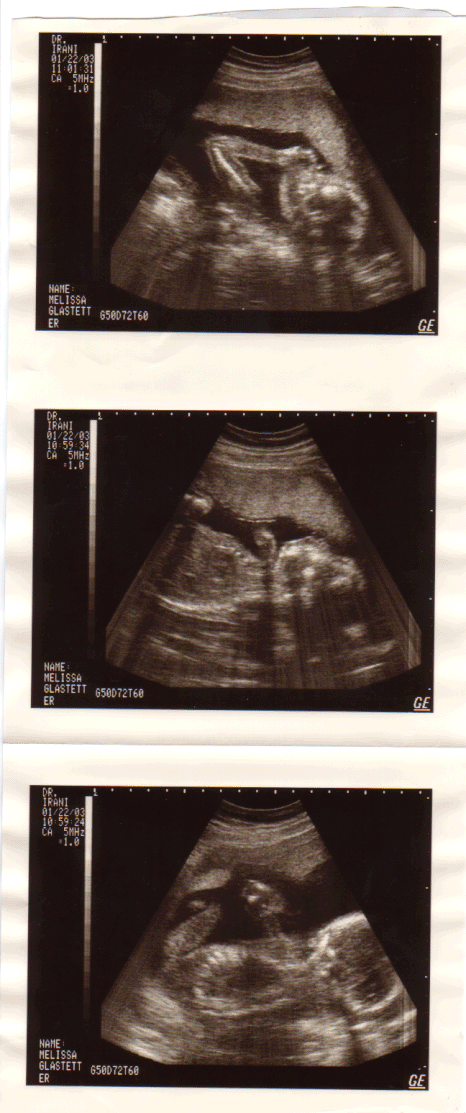

Just look at our little peanut! These were taken on January 22nd 2003.

Melissa was about 20 weeks pregnant at the time.